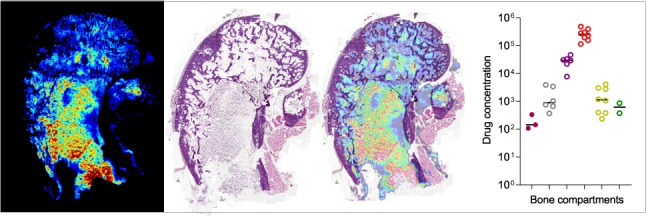

Same section MALDI MSI of bedaquiline and histology staining

To correlate spatial quantitation with histologically defined regions and to confirm the spatial quantitation data obtained by LCM in rabbit bones, we carried out MS imaging of bedaquiline in femur sections directly adjacent to those used for LCM spatial quantitation (Fig. 1). Our workflow was developed to enable H&E staining on the same section used for MSI (Fig. 5a, top left). This will be of vital importance when carrying out investigations directed at drug penetration into infected bone tissue as this can help inform on therapeutic efficacy based on the local microenvironment. Bedaquiline and its major metabolite, desmethyl bedaquiline, were detected with highest abundance in the red marrow, followed by the spongy bone, with low signal detected in a few regions of cortical bone (Fig. 5a, top middle and right panel). Matrix ions are known to cluster and form adducts with components of cortical bone, such as fragment ions of hydroxyapatite, when DHB is used as the matrix [20]. As the imaging data were acquired over a small mass window, no intact endogenous lipids were detected that could be mapped to the spongy and cortical bone regions. Thus, to highlight the spongy and cortical bone regions, we used a matrix cluster ion and merged this ion image with bedaquiline to further demonstrate the variation in drug signal across these regions (Fig. 5a, bottom panel). The H&E and MS images were then merged and used to draw regions of interest (ROIs) for cortical bone, spongy bone and bone marrow (Fig. 5a, bottom left). The average ion spectra of bedaquiline and desmethyl bedaquiline in the three regions of interest, and the characteristic signature of the naturally occurring bromine isotopes (79Br and 81Br) in bedaquiline and its metabolite (Supplementary Fig. 5), are shown in Fig. 5b. To generate semi-quantitative data from these ion maps, the individual pixel intensities from the ROIs were plotted (Fig. 5c), confirming the partitioning of bedaquiline visualized by MSI and consistent with the spatial quantitation of bedaquiline by LCM (Fig. 4).

Fig. 5.

Semi-quantitative imaging of bedaquiline in rabbit femur compartments by MALDI mass spectrometry. (a) Top row: H&E-stained section and corresponding MALDI MS images of bedaquiline and its active metabolite (desmethyl bedaquiline). Lower left: delineation of the three major regions of interest based on H&E staining and MS images: cortical bone, spongy bone and red marrow; MS image of a matrix cluster ion at m/z 656.0529; and a merged ion image of bedaquiline and the matrix ion. (b) Average ion spectra of bedaquiline and desmethyl bedaquiline in the three regions of interest outlined in (a), showing the characteristic signature of the two naturally occurring bromine isotopes (c) Scatter plots of relative pixel intensities within the three regions of interest outlined in (a)